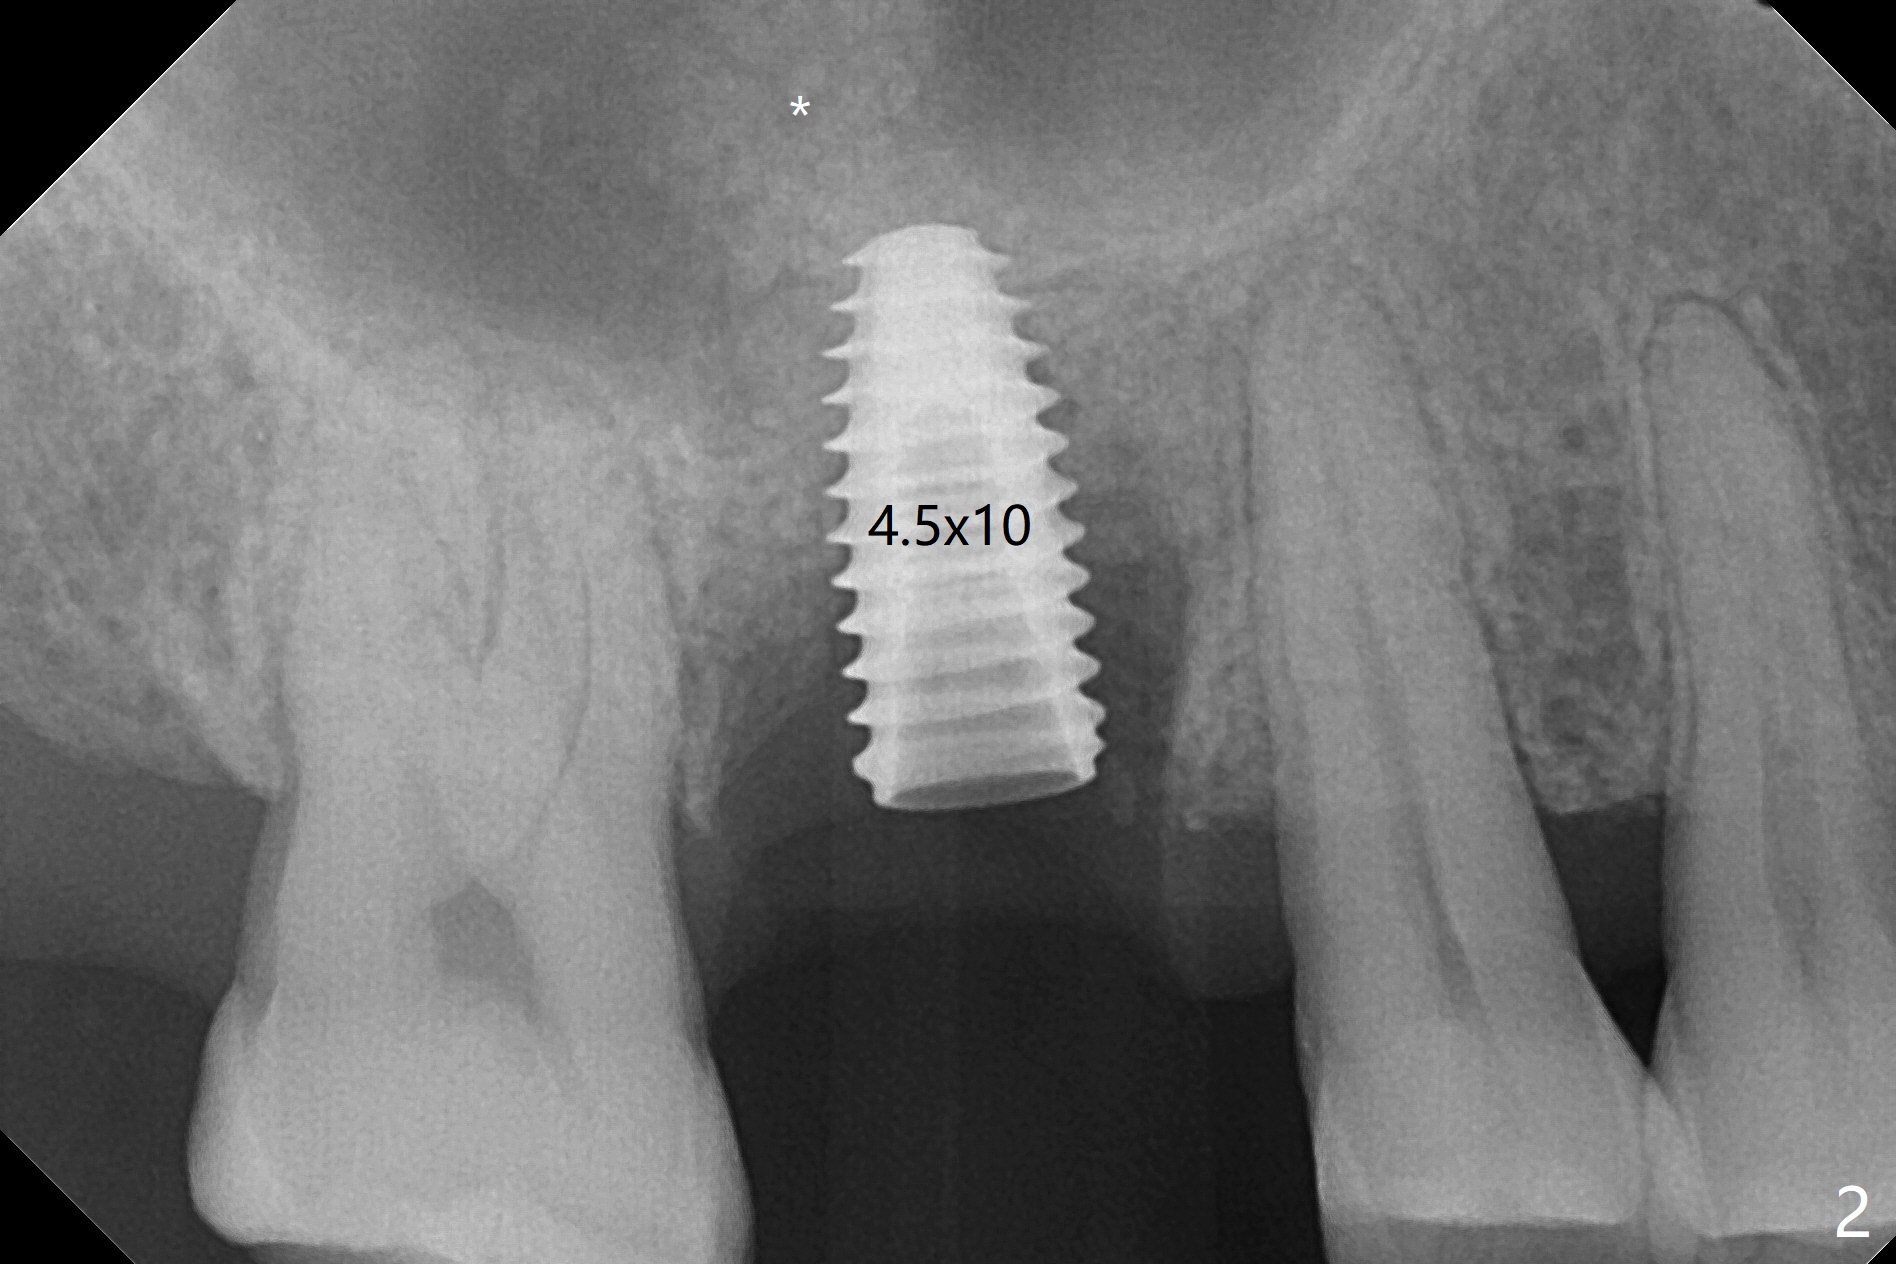

60岁男以前就害怕牙科治疗,一年前做一侧肾上腺切除,现在更紧张,不过挺配合。右上6手机切断拔除,虽然近中颊侧牙槽窝破坏厉害,中隔还很大(图一:S),利用导板顺利完成钻洞和提升术(图二:*)。植入正式植体后,放置第一轮粘性骨粉,至植体水平(确保植体深部周围没有缺失)而不影响基台置入,近中有不足之处(图三:*),第二轮骨粉补充(图四),最后覆盖PRF膜,临时牙冠固定。The crown/abutment/implant are found to have mild mobility 4.5 months postop, as related to #19 infection. A healing screw is placed. One month later, the wound heals; the bone density in the sinus increases (Fig.5 *), while that coronal to the implant decreases (^).愈合帽放置4个月,伤口还没有完全愈合,翻瓣后发现远中螺纹表面肉芽组织覆盖,去除后者,第一螺纹暴露。放置愈合基台后,从颊侧往远中缺陷填入骨粉(图六:*),缝合,覆盖树脂敷料。